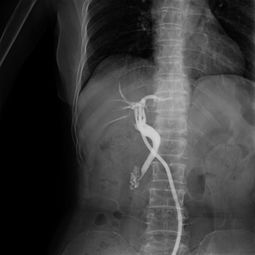

病情分析:您好,造影一般在月經(jīng)干凈后第三天至第五天做,做之前最好是不要性交. 意見(jiàn)建議:做完造影最好是隔一個(gè)月再計(jì)劃懷孕,因?yàn)樽龅臅r(shí)候有照X光.祝心情愉悅.病情分析: 您好,對(duì)于檢查輸卵管是否阻塞通暢,最好是做:動(dòng)態(tài)數(shù)字化子宮輸卵碘油造影響,它是 在全程無(wú)痛的情況下完成的,對(duì)于輕微阻塞的輸卵管能起到疏通治療的作用.并且患 者可以在第一時(shí)間看到自己的輸卵管與宮腔的形態(tài)..若是嚴(yán)重阻塞則需要手術(shù)來(lái)疏通意見(jiàn)建議: 1,必須在月經(jīng)干凈3-7天后檢查,因?yàn)榇似谧訉m內(nèi)膜較薄,不易造成子宮內(nèi)膜異位癥. 2,檢查之前禁止性生活. 3,在造影檢查過(guò)程中注射造影劑后,必須拍片兩次方能確定診斷您好:造影的檢查要在月經(jīng)干凈后的3-7天檢查,輸卵管分間質(zhì)部,峽部,壺腹部,傘端.輸卵管粘連,堵塞,上舉屬于器質(zhì)性的改變,藥物治療沒(méi)有明顯的改變,手術(shù)治療效果明顯,一般可采取宮腔鏡,腹腔鏡,輸卵管鏡治療,創(chuàng)傷小,恢復(fù)快可以在專(zhuān)家的指導(dǎo)下盡快受孕.y病情分析: 您好,很高興為您解答意見(jiàn)建議:造影一般在月經(jīng)干凈后第三天至第五天做,做之前最好是不要同房. 做完造影最好是隔一個(gè)月再計(jì)劃懷孕,因?yàn)樽龅臅r(shí)候有照X光. 生活護(hù)理:祝您早日康復(fù)身體健康您好: 受孕是個(gè)很復(fù)雜的生理過(guò)程.它要求精卵相合形成受精卵,最后著床于宮腔.除了要有正常的精子,卵子和適當(dāng)?shù)淖訉m內(nèi)環(huán)境外,使精子,卵子能夠相遇并順利運(yùn)送到宮腔也是受孕經(jīng)過(guò)中一個(gè)重要的環(huán)節(jié).這個(gè)任務(wù)是由輸卵管來(lái)完成的.如果輸卵管有炎癥,導(dǎo)致輸卵管堵塞,精子不能通過(guò)與卵子相遇造成的不孕,則稱(chēng)為輸卵管阻塞性不孕.輸卵管根據(jù)形態(tài)由內(nèi)向外分為四部分:間質(zhì)部,峽部,壺腹部,傘部.在臨床上,有80%的不孕癥患者是由于輸卵管因素而造成.輸卵管阻塞常因人工流產(chǎn),自然流產(chǎn),藥流,引產(chǎn),不潔性交,盆腔感染等引起輸卵管壁粘連,充血,水腫而阻塞,導(dǎo)致精子與卵子不能夠結(jié)合,最終導(dǎo)致不孕癥.建議您到專(zhuān)科醫(yī)院就診,明確病情嚴(yán)重程度后在選擇合適的治療方案進(jìn)行疏通.W病情分析: 輸卵管造影前注意事項(xiàng)意見(jiàn)建議: 1,必須在月經(jīng)干凈3-7天后檢查,因?yàn)榇似谧訉m內(nèi)膜較薄,不易造成子宮內(nèi)膜異位癥. 2,檢查之前禁止性生活.3,在造影檢查過(guò)程中注射造影劑后,必須拍片兩次方能確定診斷.。